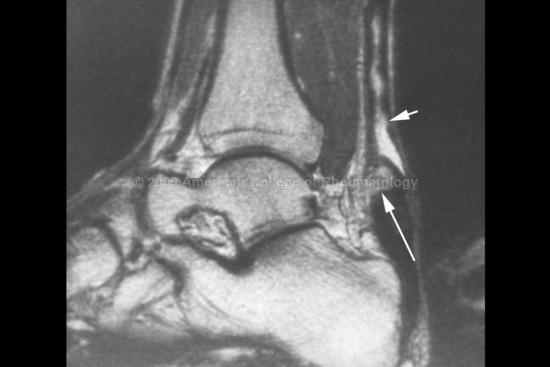

△ 후경골근건(초록색 화살표)의 거대화와 주상골(N)의 골수종

△ 정상적인 장지굴근건(노란색 화살표)과 장모지굴근건(분홍색 화살표)